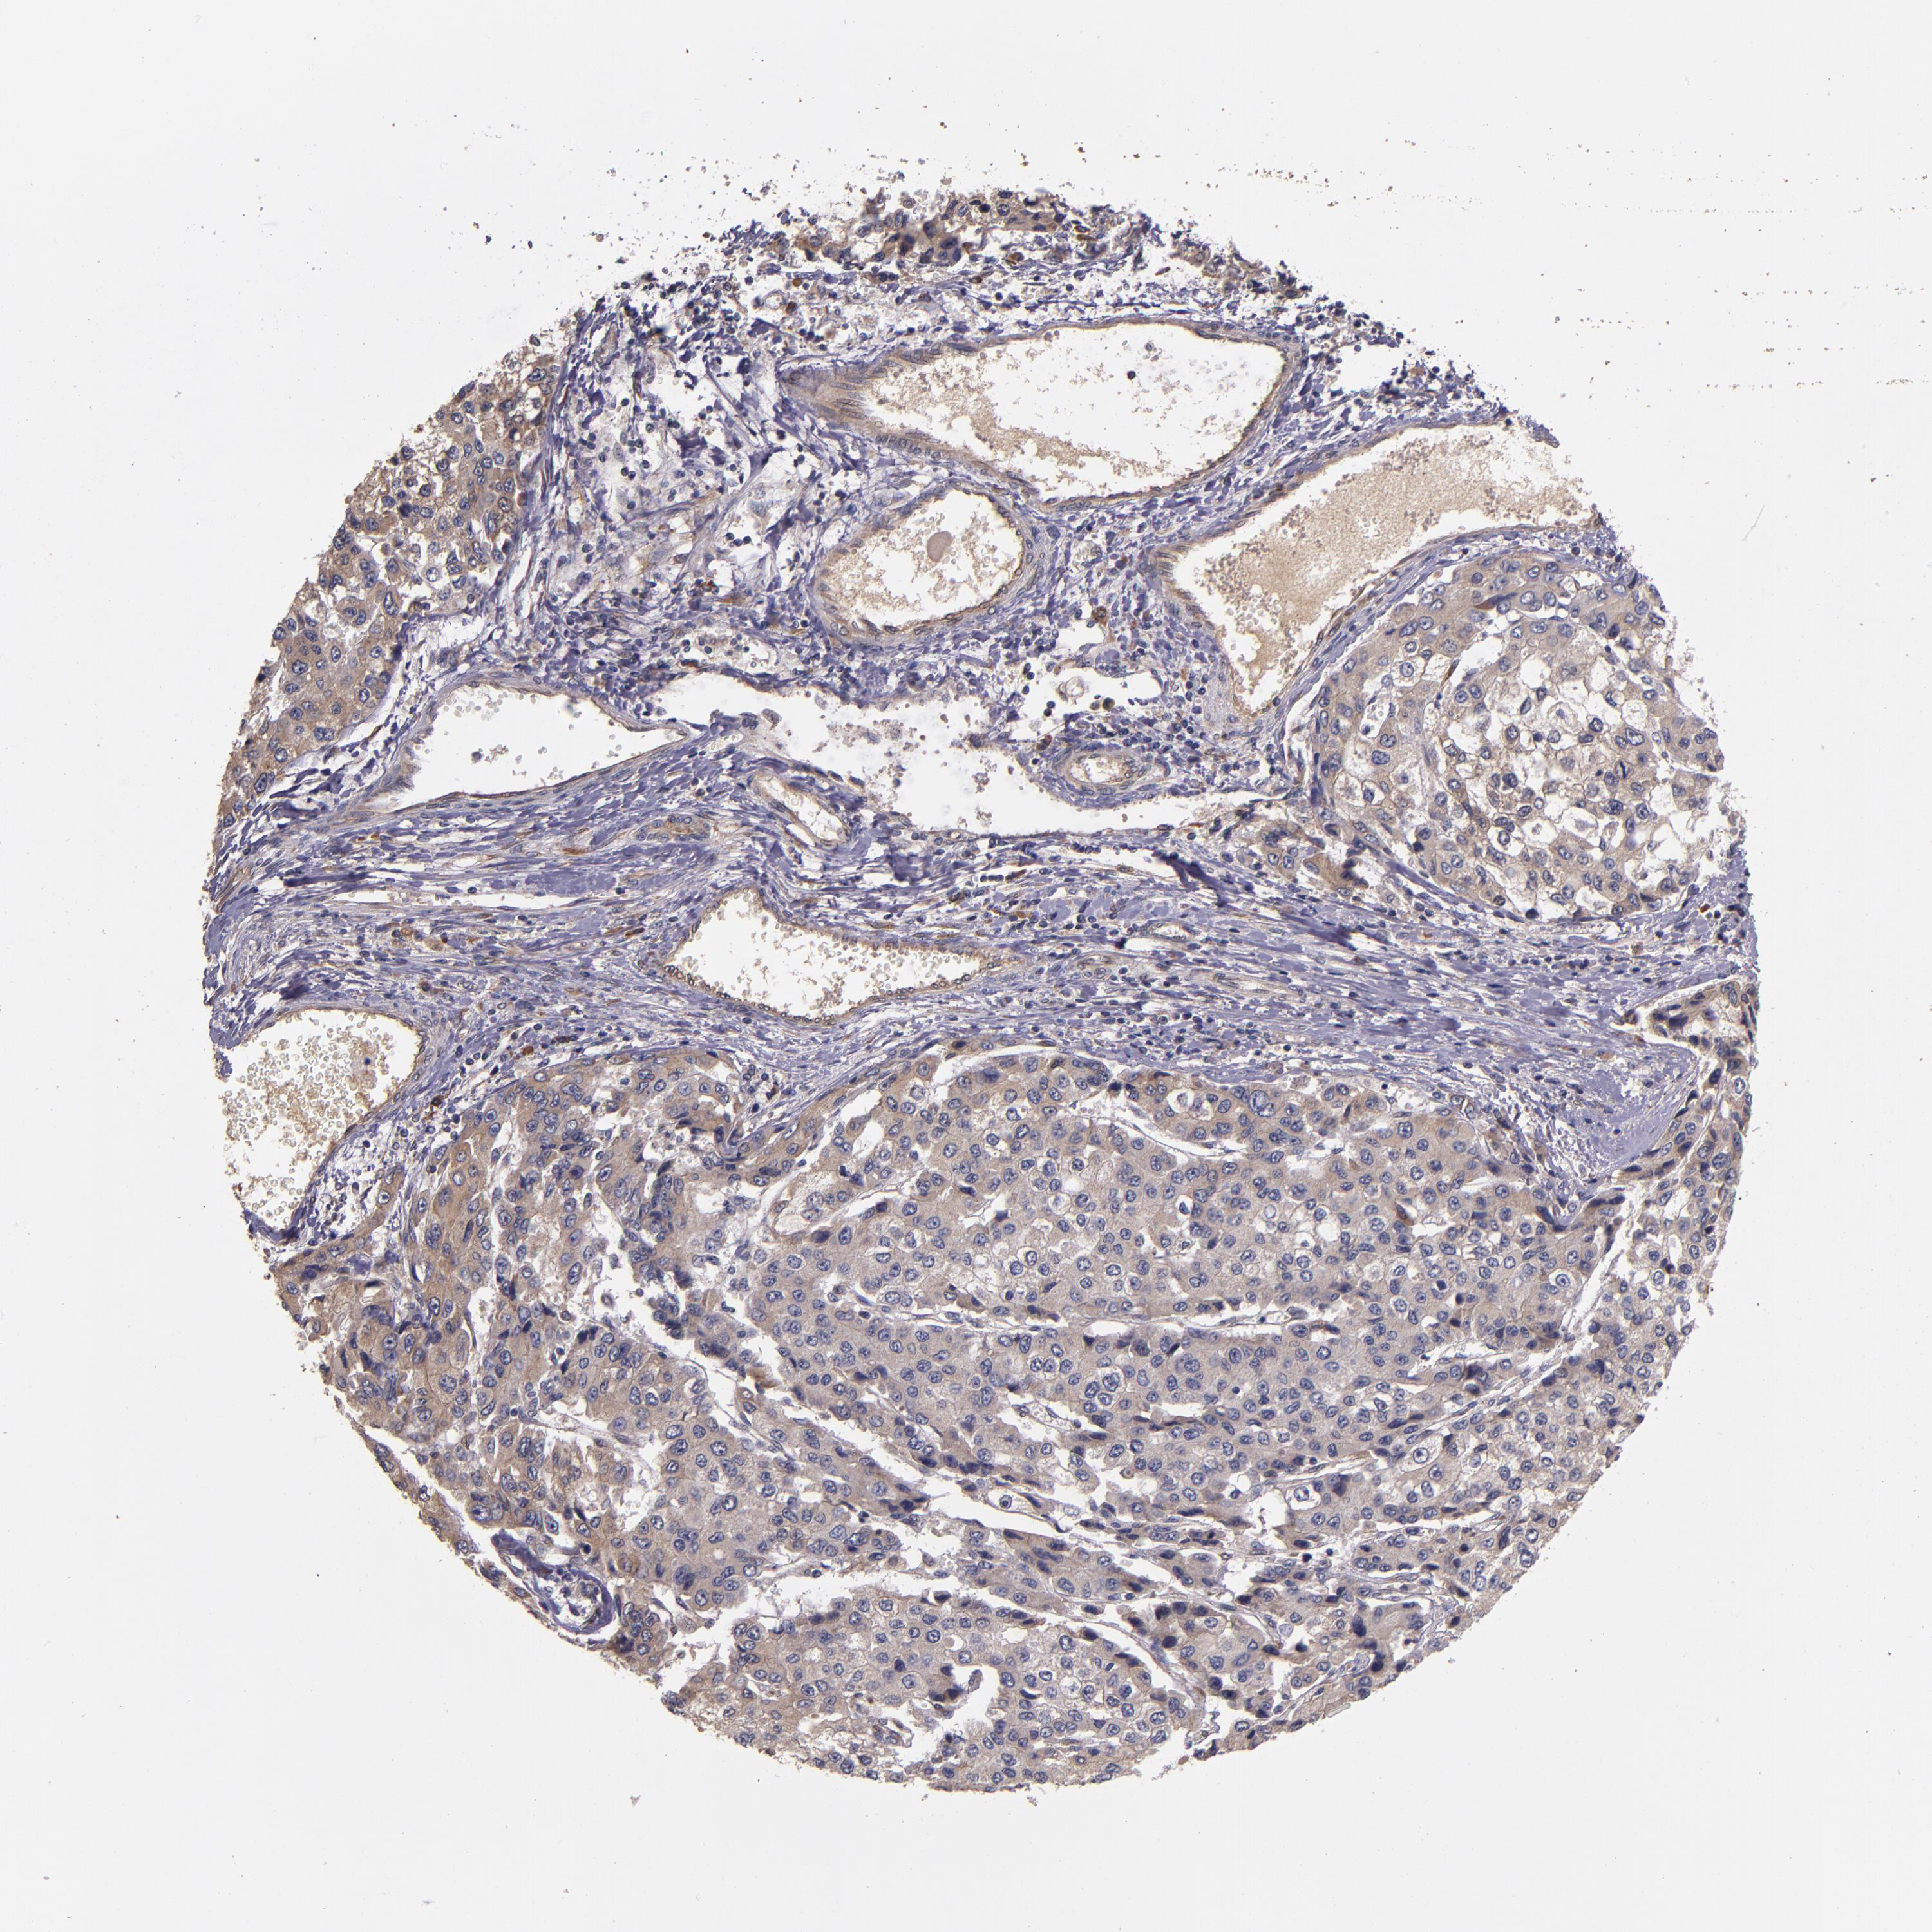

LIVER CANCER - Protein expressioni

A mouse-over function shows sample information and annotation data. Click on an image to view it in a full screen mode. Samples can be filtered based on level of antibody staining by selecting one or several of the following categories: high, medium, low and not detected. The assay and annotation is described here.

Note that samples used for immunohistochemistry by the Human Protein Atlas do not correspond to samples in the TCGA dataset.

Antibody stainingi

Antibody staining in the annotated cell types in the current human tissue is reported as not detected, low, medium, or high, based on conventional immunohistochemistry profiling in selected tissues. This score is based on the combination of the staining intensity and fraction of stained cells.

Each image is clickable and will lead to virtual microscopy that enables deeper exploration of all samples and also displays staining intensity scores, fraction scores and subcellular localization as well as patient and tissue information for each sample.

Antibody HPA002859

Antibody CAB011655

Staining

High

Medium

Low

Not detected

Intensity

Strong

Moderate

Weak

Negative

Quantity

>75%

75%-25%

<25%

None

Location

Nuclear

Cytoplasmic/membranous

Cytoplasmic/membranous,nuclear

Carcinoma, Hepatocellular, NOS

Cholangiocarcinoma